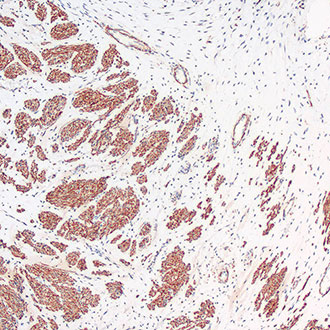

p63

p63 -